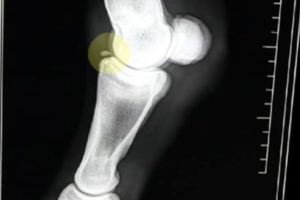

Bone chip in the knee: When you have some injury in your knee joint which is an injury of your cartilage or your bones in the knee, then this condition is known as bone chip in the knee. When you are suffering from this condition, then the cartilage which is covering the patella or the femur is affected. When some parts of the bones or the cartilage is lost, then they can float in the knee area. Osteochondral fracture and chondral fracture are other terms for this condition. Also the part of the bones and cartilage which are lost are known as joint mouse or loose bodies. [2]

- The cause for the bone chip in the knee: This condition is result from the knee injury which is caused by a piece of cartilage or bone which is chipped from the back of the kneecap or from the end of the thighbone. When you are having serious injuries in your knees, then you are having the biggest chances to get bone chip in the knee. Also when you have small injuries which are repeating constantly, then you also have increased chances for getting bone chip in the knees. Also when you are not having enough blood supply in your knees, then you have increased chances for getting this disease. [2]

- The symptoms of the bone chip in the knee: Here are the symptoms of the bone chip in the knee:

- When you are moving your knee, you are feeling a pain

- Your knees can be swollen

- Also there are some cases when you are feeling that your knees are locked (from one period to another period)

- In some cases you are feeling chips in the surface of your knees

- In the surface of your knees you are also having chances to have bulges

- You will not have a chance to straighten your knees or you are not having a chance to fully bend your knees

If you are feeling some of these symptoms, then you should visit your doctor. He or she will make tests to be sure for your condition such as MRI and X-rays of your knees [3,4]. You should not be active until your symptoms are gone. You should rest your knees [5]. It might take several weeks until your symptoms have gone. In some cases these symptoms are not gone by their own and in those cases surgery [2] is recommended because it will make their condition better. You should visit your doctor at the first moment when you have started feeling these symptoms. You should also take care about your knees in your home. This bone chip is not easily prevented, so you must talk with your doctor about it.